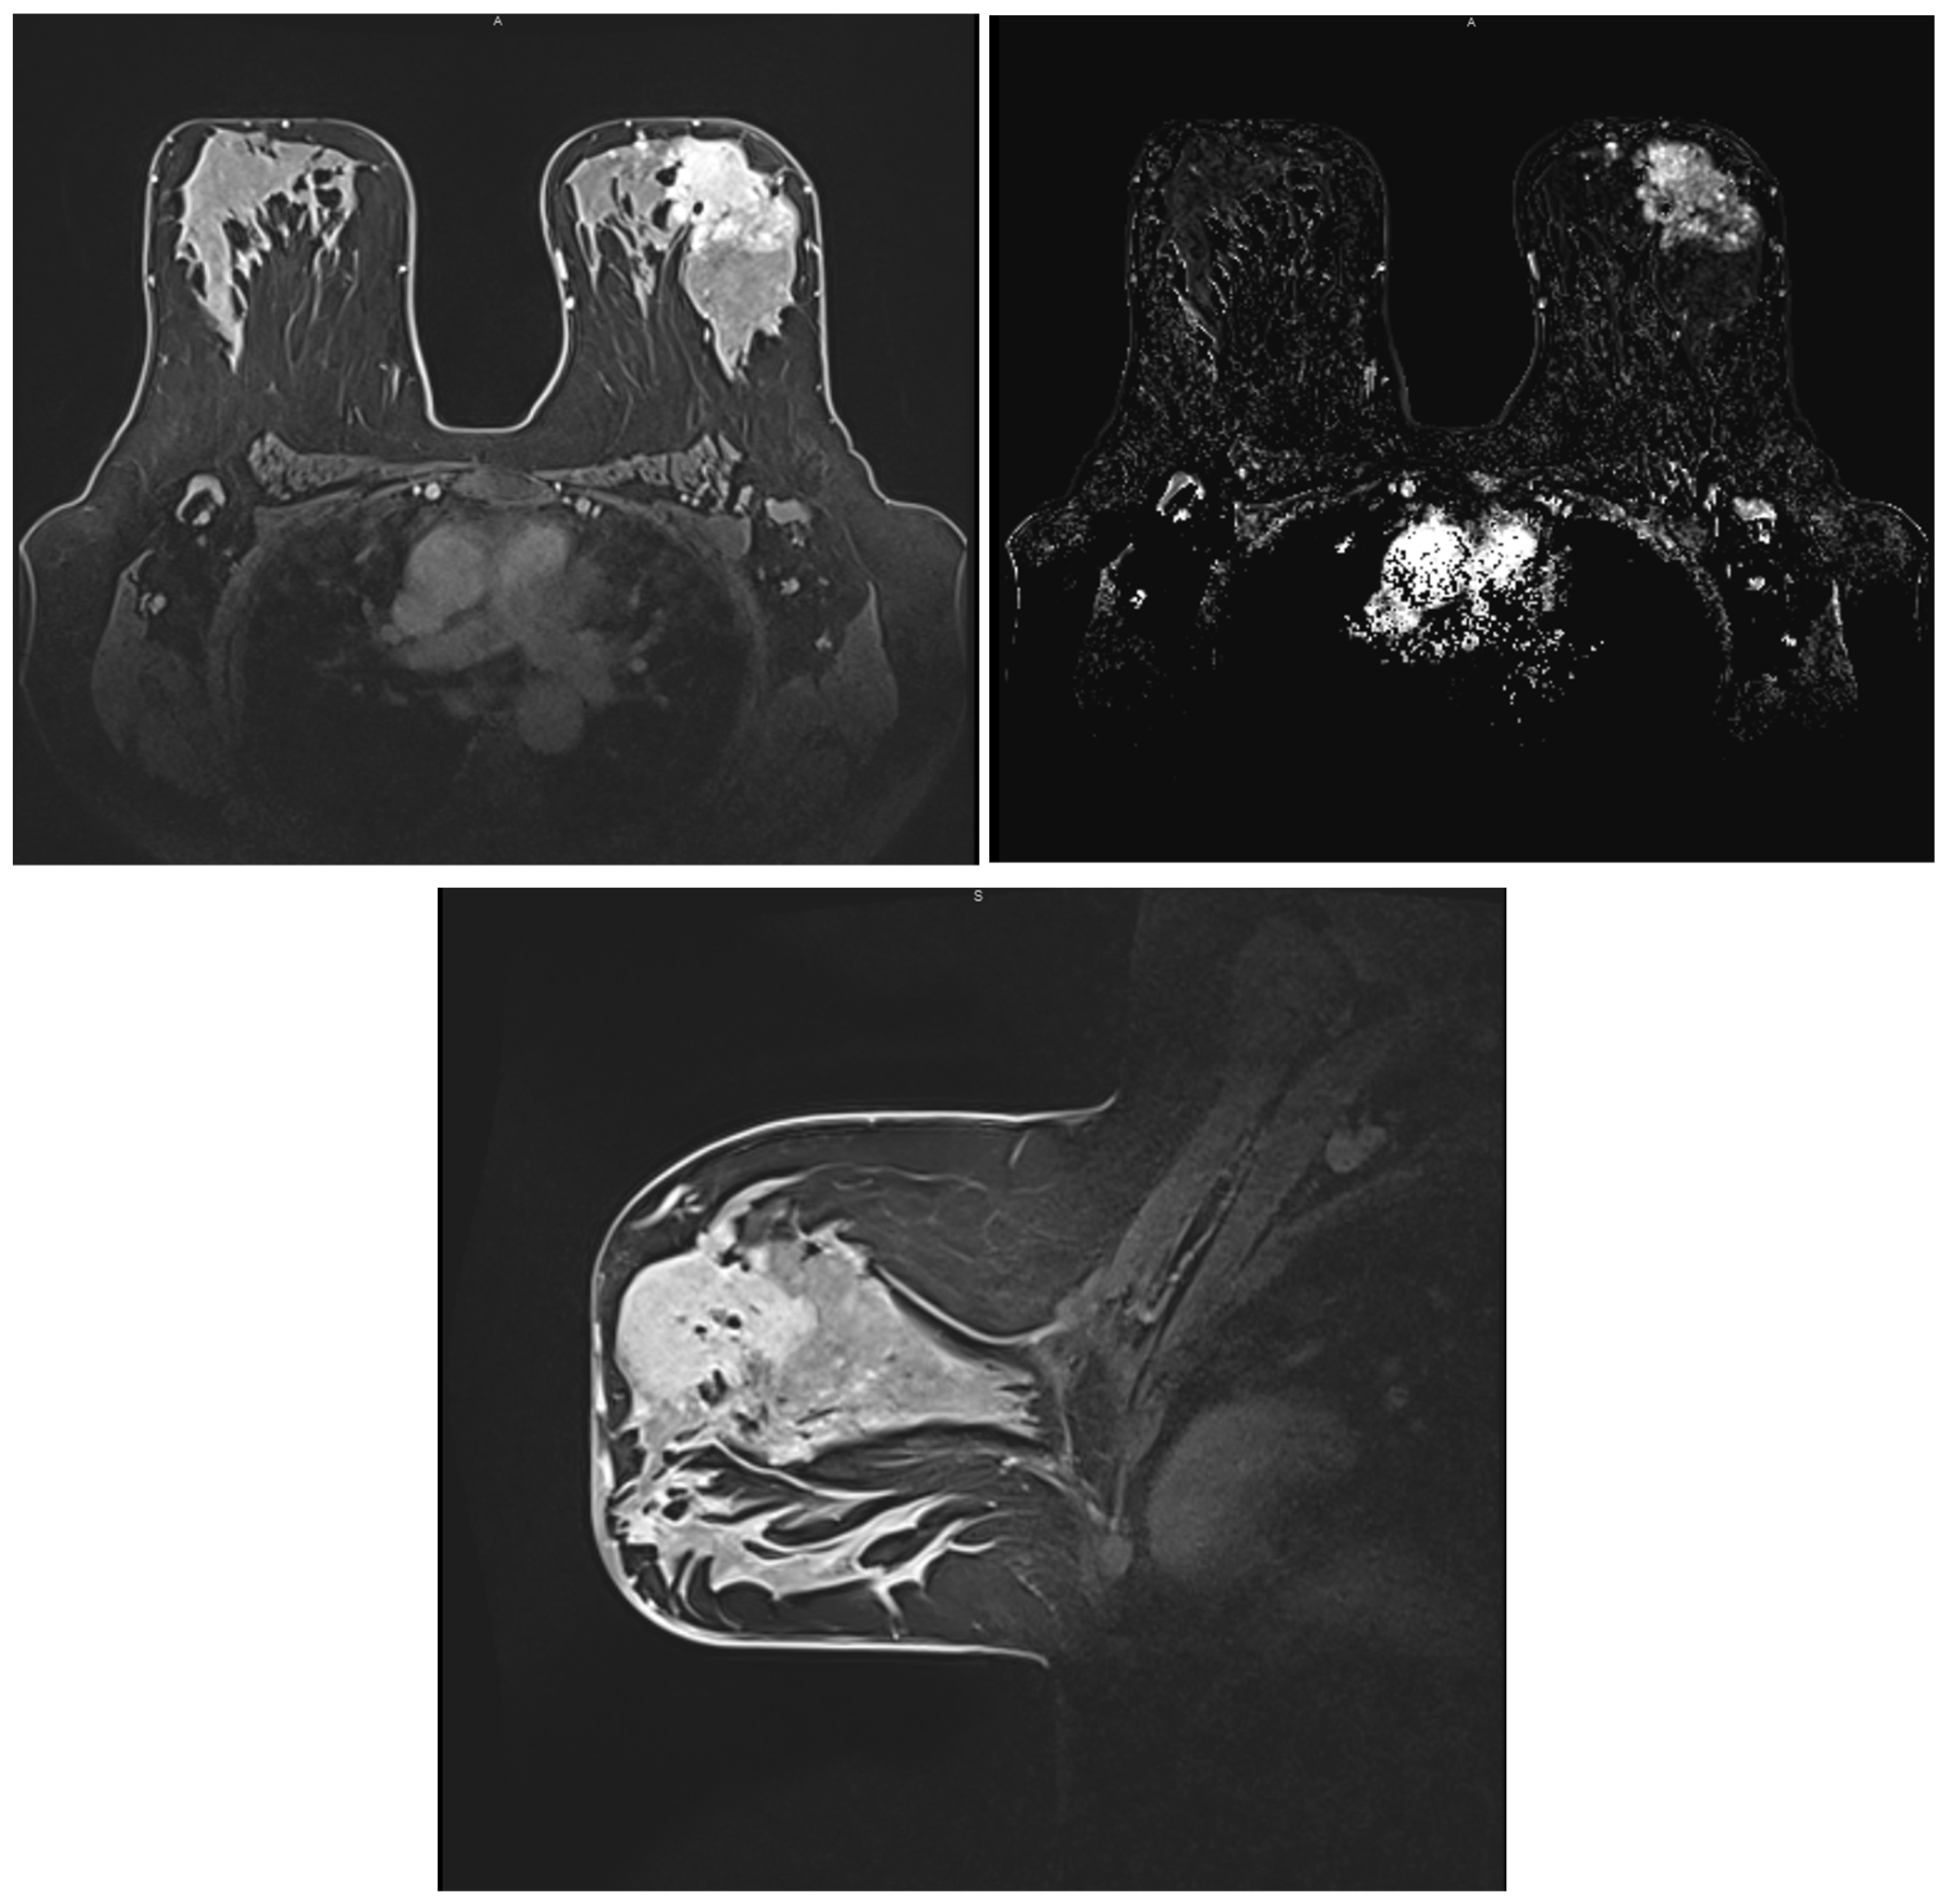

2.4. Magnetic Resonance Imaging (MRI)